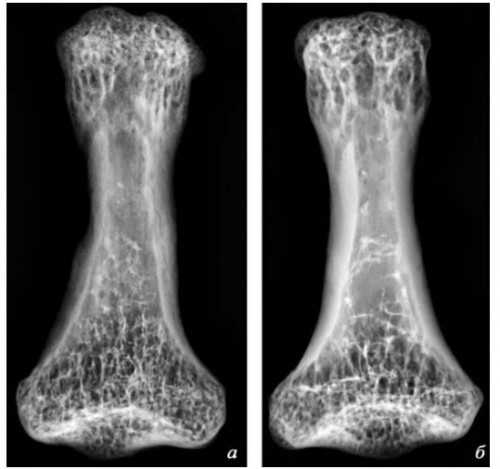

Хорошо сохранившиеся останки пожилого мужчины найдены в 2007 г. на неолитическом памятнике Бютье-Буланкур (70 км к югу от Парижа), их возраст 6900—6700 лет. Сразу было замечено, что часть левого плеча отсутствует, кости предплечья и кисть тоже — при том, что правая рука сохранилась практически полностью, как и весь скелет. На врождённое отсутствие руки не похоже — в этом случае наблюдалось бы утончение кости, а его нет. Ампутация? Рентген и микротомография показали: поверх травмы сформировался новый кортикальный слой. Судя по его толщине, после операции человек прожил от нескольких месяцев до нескольких лет. Признаков инфекционного поражения нет — всё было сделано аккуратно. Дядька не молод; при жизни он потерял все зубы, на позвонках и коленях — многочисленные признаки артроза.

Погребение 416, Бютье-Буланкур, Франция. Источник: Buquet-Marcon 2007, p. 15

Сравнение 3-х микротомографий плечевой кости из Погребения 416, Бютье-Буланкур, с микротомографией плечевой кости современного человека. Источник: Buquet-Marcon 2007, p. 15, p. 17.

Что же послужило причиной для операции? Возможно, травма руки. Исследователи полагают, что рука была частично оторвана в результате несчастного случая, и хирург просто завершил ампутацию. Такой вывод сделан, поскольку место для ампутации выбрано не лучшее — проще было бы резать в нескольких сантиметрах от локтевого сочленения, на диафизе — а рубили прямо по блоку сустава. Однако, судя по всему, кость не была полностью сломана. Чтобы провести такую операцию, древний хирург должен был уметь быстро остановить кровь и провести дезинфекцию.